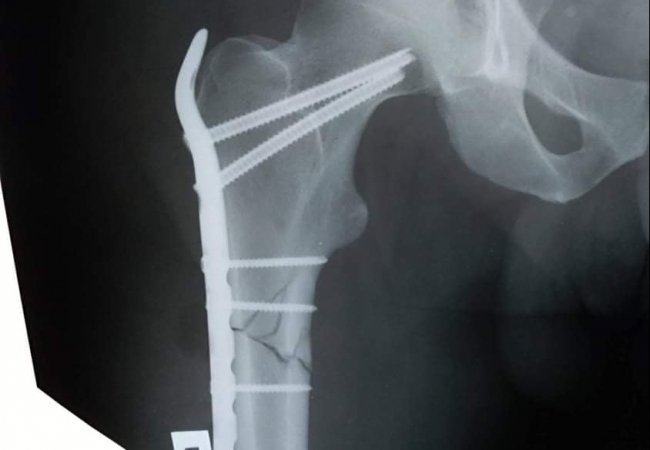

У процесі надання першої медичної допомоги йому встановили діагноз: закритий багатовідламковий перелом верхньої третини правої стегнової кістки із зміщенням уламків. Про це інформують на сторінці закладу у facebook.

Після дообстеження та передопераційної підготовки 18 грудня чоловіку провели операцію - відкриту репозицію МОС (металосинтез) правої стегнової кістки проксинальною LCP пластиною та гвинтами.

Складну операцію, яка тривала протягом трьої годин, успішно проведели лікарі-травматологи: Босий Т.Б., Радчук В.М., та Лотоцький І.А.